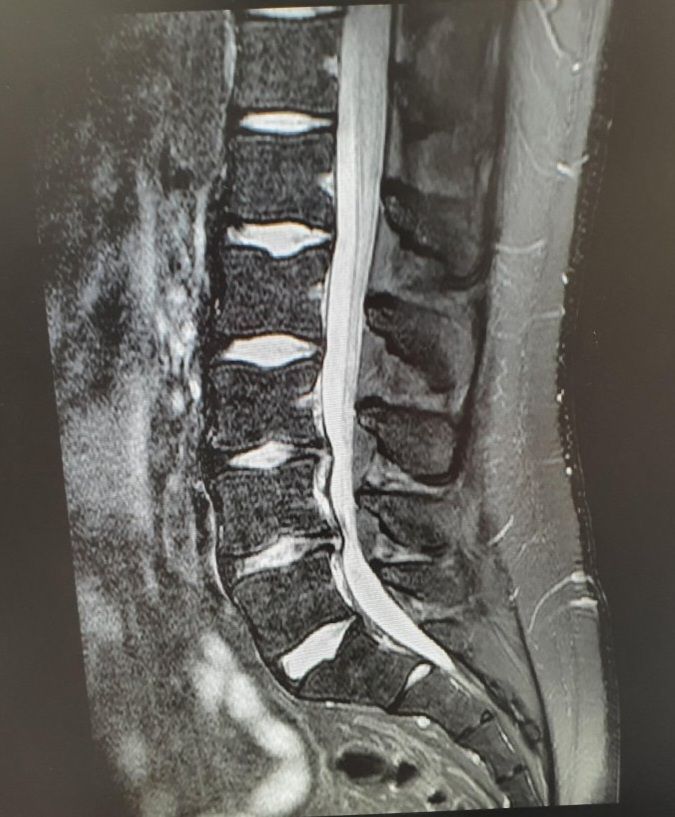

이거 허리 상태가 어느정도인건가요? (사진)

디스크가 터졌단건 들었는데 오늘 일때문에 시간이 없어서 상태가 정확히 어떤지는 정확하게 못들었거든요..

대략이라도 좋으니까 상태가 어떤지 알 수 있을까요?

한장으로 명확한 상태를 파악하기는 힘들지만

요추 3-4-5 사이의 디스크에 의한 신경압박이 일부 보입니다.

심한 양상은 보이지 않아, 주사 및 약물, 물리치료 등을 시행하시면서 경과관찰이 가능할 것 같습니다.

이 한컷으로만 판단할 수 없고 MRI를 다 봐야 정확한 설명이 가능합니다.

이 사진만 봐서는 나쁘지 않습니다. 디스크 섬유륜이 조금씩 찢어진건 보이지만 방사통을 유발할만큼 탈출이 있어보이지는 않습니다. \

요추전만 자세만 잘 취해주시면 회복이 가능할거라고 생각됩니다.